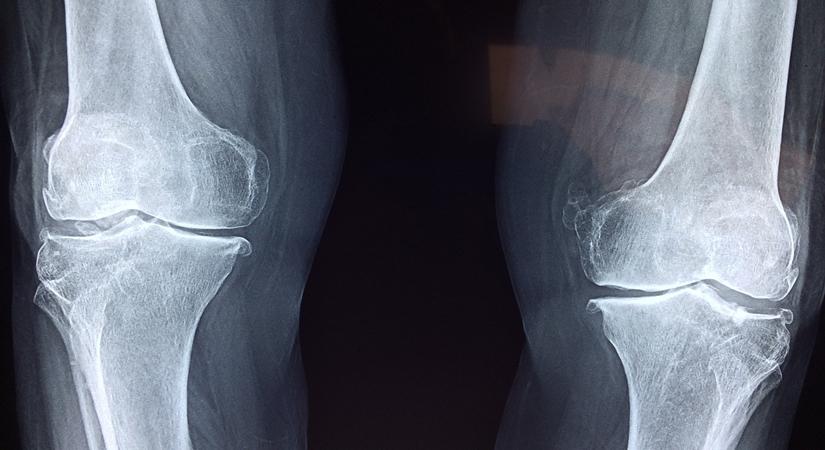

“Joint and muscle pain can also be experienced by doing chores or activities that you haven’t frequently done before like sitting cross-legged on the floor, bending from the waist while cleaning or cooking, lifting heavy weights, etc. It has been observed that reduced physical movement has led to increase in pain in the waist and back, legs, knees and hips,” underlines the expert.

• If you experience swollen knees, then you can tie a cloth or crepe bandage around it. You may also use a kneecap for the same